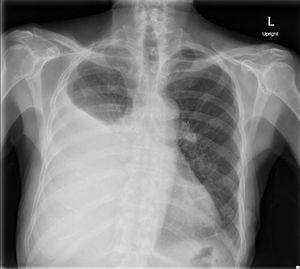

What's your diagnosis??!!

1.pleural effusion 2.pneumothorax 3.emphysema 4.pulmonary edema 5.sarcoidosis

It a a pleural effusion but it is a large effusion and in this case it may cause mediastinal shift away from the affected side....

Right pleural effusion